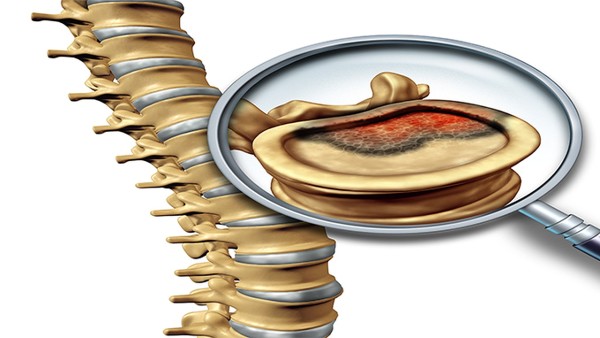

骨折二次复位的最佳时间

骨折后复位的最佳时间